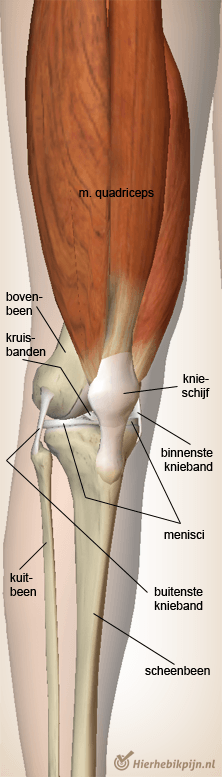

Anatomy of the knee

The structure of the knee can be confusing for many people. Terms such as 'meniscus', 'knee ligaments', and 'cruciate ligaments' are often used interchangeably. Below is an overview of the main structures in and around the knee.

Thigh bone and shin bone

Different bones meet in the knee joint. The rounded joint surfaces of the thigh bone (the femur) rest on the flatter top of the shin bone (the tibia). Together they form the 'tibiofemoral joint'. Because the joint surfaces of the thigh bone do not fit perfectly on the flat 'tibial plateau', there are two menisci (plural of 'meniscus') between the bone ends.

Meniscus

A meniscus is a crescent-shaped cartilage disc that helps distribute pressure in the knee joint and acts as a shock absorber. It is also thought that the menisci contribute to better lubrication of the joint by optimally guiding the joint fluid (synovia) along the joint cartilage.

Ligaments

The stability of the knee is largely provided by various ligament structures. They hold the knee firmly together without restricting its natural movements.

Between the inner (medial) and outer (lateral) meniscus are the anterior and posterior cruciate ligaments. These should not be confused with the inner (medial) and outer (lateral) collateral ligaments, which are located on either side of the joint.

Kneecap

The 'patella', better known as the kneecap, protects the front of the knee and plays an important role in helping the quadriceps muscle transfer forces to the lower leg. The patella forms a separate joint with the femur, also known as the 'patellofemoral joint'.

Fibula

On the outside of the knee is a small joint formed by the head of the fibula firmly connected to the tibia. This is called the tibiofibular joint (tibia = shin bone, fibula = calf bone).

Muscles

The muscle that runs from the hip along the front of the thigh and then via a tendon attaches with the kneecap to the lower leg is the quadriceps muscle. This muscle functions to extend the knee.

At the backside of the knee and the thigh are the hamstrings. The main function of the hamstrings is to bend the knee. Together with many other muscles, the quadriceps and hamstrings work closely to allow smooth rotation, bending, and extension of the knee.